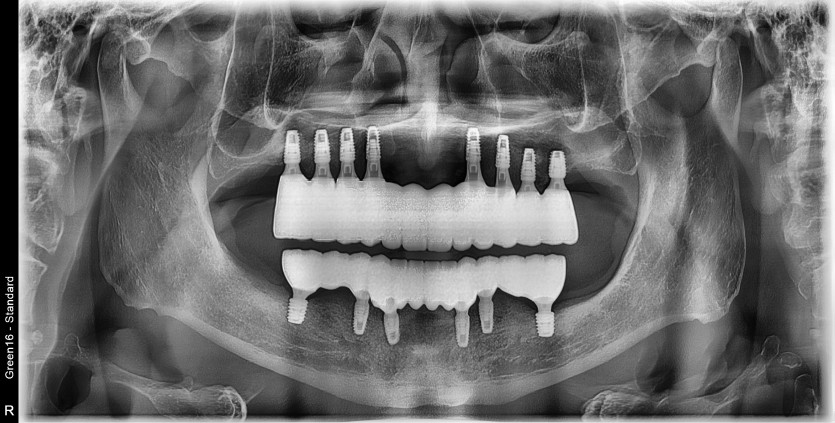

만 68세 전체 임플란트 증례

전체 임플란트 증례입니다.

14개의 임플란트로 완성하였습니다.